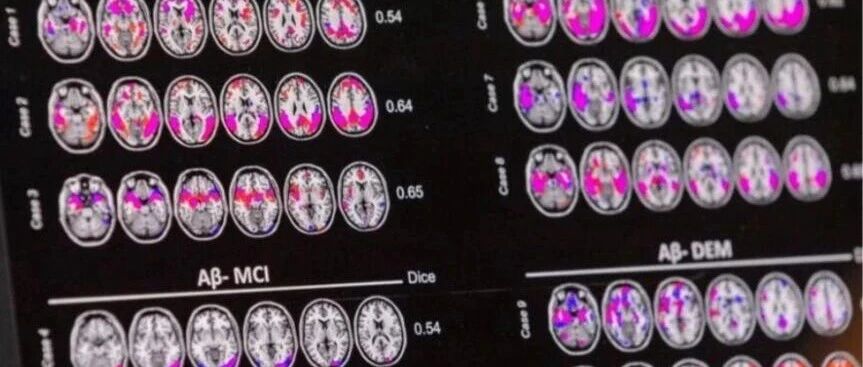

Core Viewpoint - The article discusses the advancements in early detection of Alzheimer's disease (AD) through blood tests, highlighting the approval of new diagnostic tools that could significantly improve screening and monitoring for the disease [3][4]. Group 1: Blood Test Approvals and Developments - Roche Diagnostics received approval for its Alzheimer's blood test reagent in Hainan Province, China, which will be used clinically to exclude Alzheimer's-related amyloid pathology [3]. - The FDA approved Roche's blood test for use in primary care settings, achieving a diagnostic accuracy of 97.9% in a clinical trial involving 312 participants [3]. - Fujirebio's Alzheimer's blood test also received FDA approval and plans to enter the Chinese market in collaboration with partners [3]. Group 2: Importance of Early Detection - Alzheimer's disease accounts for 60% to 80% of all dementia cases globally, making early diagnosis crucial for effective treatment [5]. - The new blood testing methods are expected to facilitate early diagnosis and screening, allowing patients to receive treatment sooner [5]. - Traditional diagnostic methods, such as lumbar punctures and PET scans, are expensive and uncomfortable, presenting challenges for widespread clinical testing [5]. Group 3: Clinical Applications and Guidelines - Blood biomarkers for Alzheimer's have two main clinical uses: as a triage tool to determine the need for further testing and for direct pathological identification of amyloid proteins [6]. - The sensitivity and specificity thresholds for blood biomarkers are set at 90% and 75% respectively for triage testing, and both must exceed 90% for direct pathological identification [6]. - Despite the approval of several blood tests, they cannot yet serve as standalone diagnostic tools for Alzheimer's disease [6].

Core Viewpoint - The adoption of blood testing methods for Alzheimer's disease (AD) will facilitate early diagnosis and screening, allowing patients to receive treatment sooner. Current AD drugs on the market are effective only for early-stage patients [1][4]. Group 1: Blood Testing Developments - Roche Diagnostics' blood test for Alzheimer's disease has received approval from the Hainan Provincial Drug Administration for clinical use, achieving a diagnostic accuracy of 97.9% in a trial involving 312 participants [3]. - Fujirebio's blood test for Alzheimer's disease was also approved by the FDA in May 2022, with plans to introduce it to China in collaboration with partners [3]. - BGI's Alzheimer's blood test product is expected to receive approval from Chinese regulatory authorities in April 2024 and is already being promoted as an auxiliary detection tool in multiple cities [3]. Group 2: Clinical Implications and Challenges - Alzheimer's disease accounts for 60% to 80% of all dementia cases globally, highlighting the need for effective early detection methods [4]. - Traditional detection methods, such as lumbar puncture and PET scans, are expensive and uncomfortable, posing challenges for large-scale clinical testing [4]. - New blood testing methods can be combined with other diagnostic approaches, providing a cost-effective means for early screening and ongoing monitoring, especially in the elderly population [4]. Group 3: Clinical Utility of Blood Biomarkers - According to the latest guidelines from the International Alzheimer's Association, blood biomarkers serve two main clinical purposes: as a triage tool to determine the need for further PET scans or cerebrospinal fluid tests, and for direct pathological identification of amyloid proteins [5]. - A blood biomarker with sensitivity ≥90% and specificity ≥75% can be used as a triage test, while those meeting or exceeding 90% for both can replace PET imaging or cerebrospinal fluid tests for pathological identification [5]. Group 4: Current Application and Limitations - Blood testing for Alzheimer's disease is being deployed as an auxiliary method in several hospitals across China, although it cannot yet serve as an independent diagnostic criterion [6].